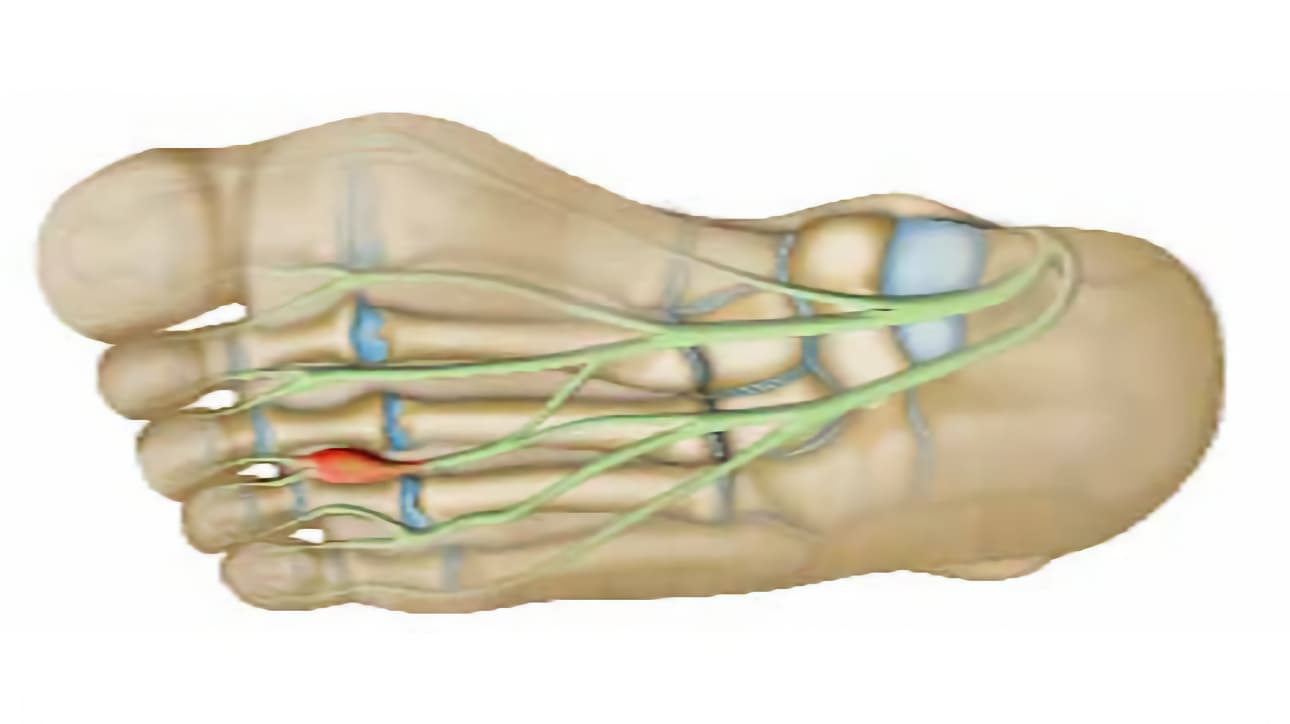

Ορισμένα νεύρα, που περνούν ανάμεσα από τους δακτύλους και ευθύνονται για την αισθητικότητά τους (αισθητικά νεύρα) συμπιέζονται.

Τα νεύρα μπορεί να συμπιέζονται είτε από τα μετατάρσια, είτε από τους θυλάκους που προφυλάσσουν την άρθρωση από τριβές (ορογόνοι θύλακοι). Ο θύλακος μπορεί να ερεθιστεί, λόγω πιέσεων (ορογονοθυλακίτιδα), να γεμίσει υγρό, να αυξηθεί ο όγκος του και να συμπιέσει το νεύρο.

Τα νεύρα περιβάλλονται από μια προστατευτική θήκη. Όταν το νεύρο πιέζεται, αμύνεται αυξάνοντας το πάχος της θήκης. Όσο όμως πραγματοποιείται πάχυνση της θήκης, τόσο οι ιστοί στο εσωτερικό συμπιέζονται και επιδεινώνεται η κατάστασή τους. Τότε εμφανίζονται οι πόνοι. Στο σημείο συμπίεσης, το νεύρο παρουσιάζει, μερικές φορές, διόγκωση. Πρόκειται για νευρίνωμα Morton. Στην ιατρική γλώσσα, το πρόβλημα αυτό αναφέρεται ως μεταταρσιαλγία Morton.